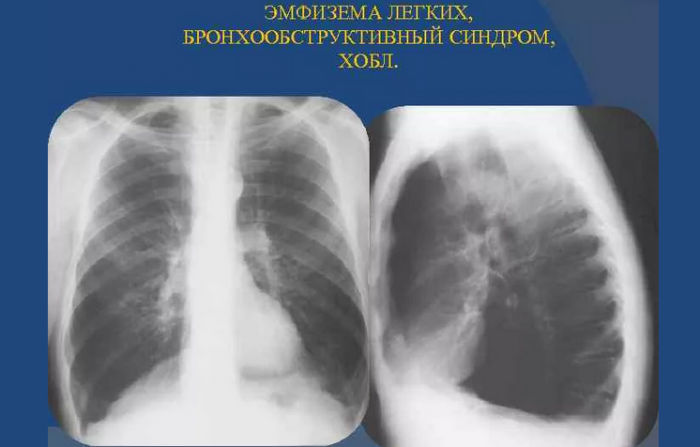

• Рентгенография